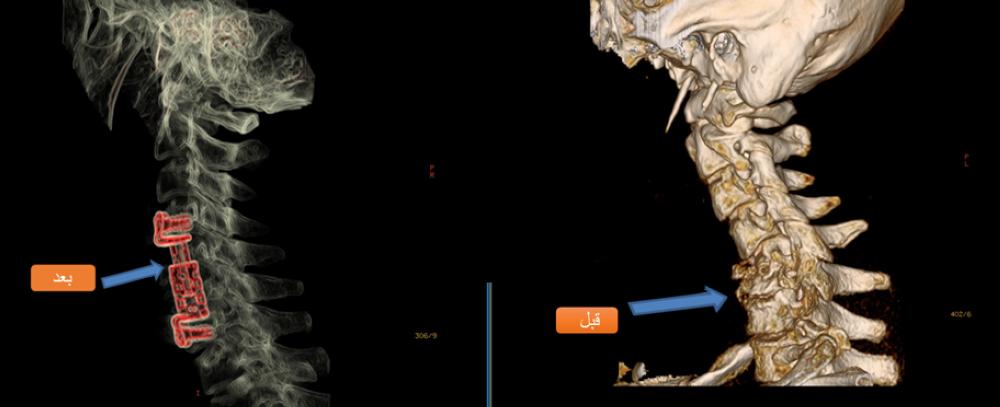

وقد دخل المريض المركز الطبي بينبع الصناعية للعلاج من مرض بكتيريا الدرن، والتي كانت تتمركز بالعمود الفقري العنقي، والتي تسببت في تفتت وانخفاس الفقرتين 5 و6 مع انحراف العمود الفقري العنقي، والذي أدى إلى الضغط الشديد على النخاع الشوكي، بعد ذلك قرر فريق الجراحة بالمركز الطبي بقيادة استشاري جراحة المخ والأعصاب والعمود الفقري الدكتور نبيه بن عبدالرحمن باجنيد، التدخل الجراحي بواسطة الميكروسكوب العصبي بإزالة الفقرتين المصابتين بالكامل، واستبدالهما بالمباعد المصنوع من مادة التيتانيوم، وإعادة العمود الفقري إلى وضعه الفيزيائي الصحيح، وتحرير النخاع الشوكي تماما.